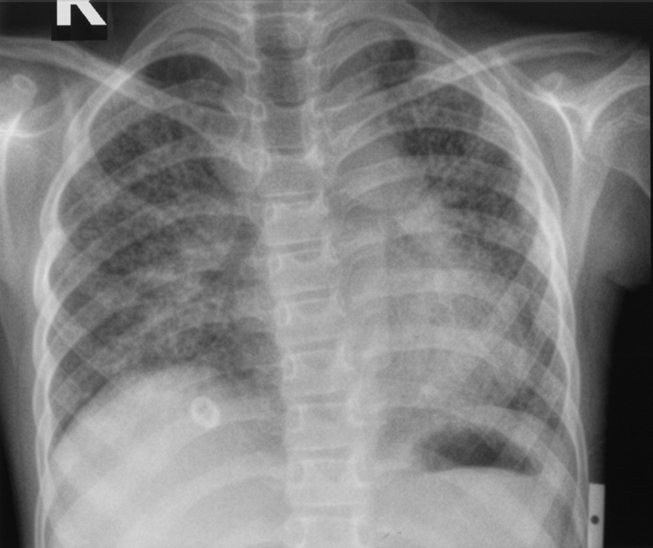

Chest radiography showed bilateral reticulonodular opacities (Figure 1). The patient was treated symptomatically and then started on ATT (Anti-tubercular treatment) under DOTS (Directly observed treatment short course) for 6 months. Routine hematological tests were normal except for leucocytosis 14800lµl. Liver function tests, renal function tests, and lipid profiles were within normal limits. The international normalized ratio was 14 and 2 sputum samples were negative for acid-fast bacilli. Antinuclear antibodies (ANA) and anti-endomysial antibodies were negative and serum angiotensin-converting enzyme (ACE) was normal (26.4).

Figure1: Chest radiograph shows bilateral reticulonodular opacities